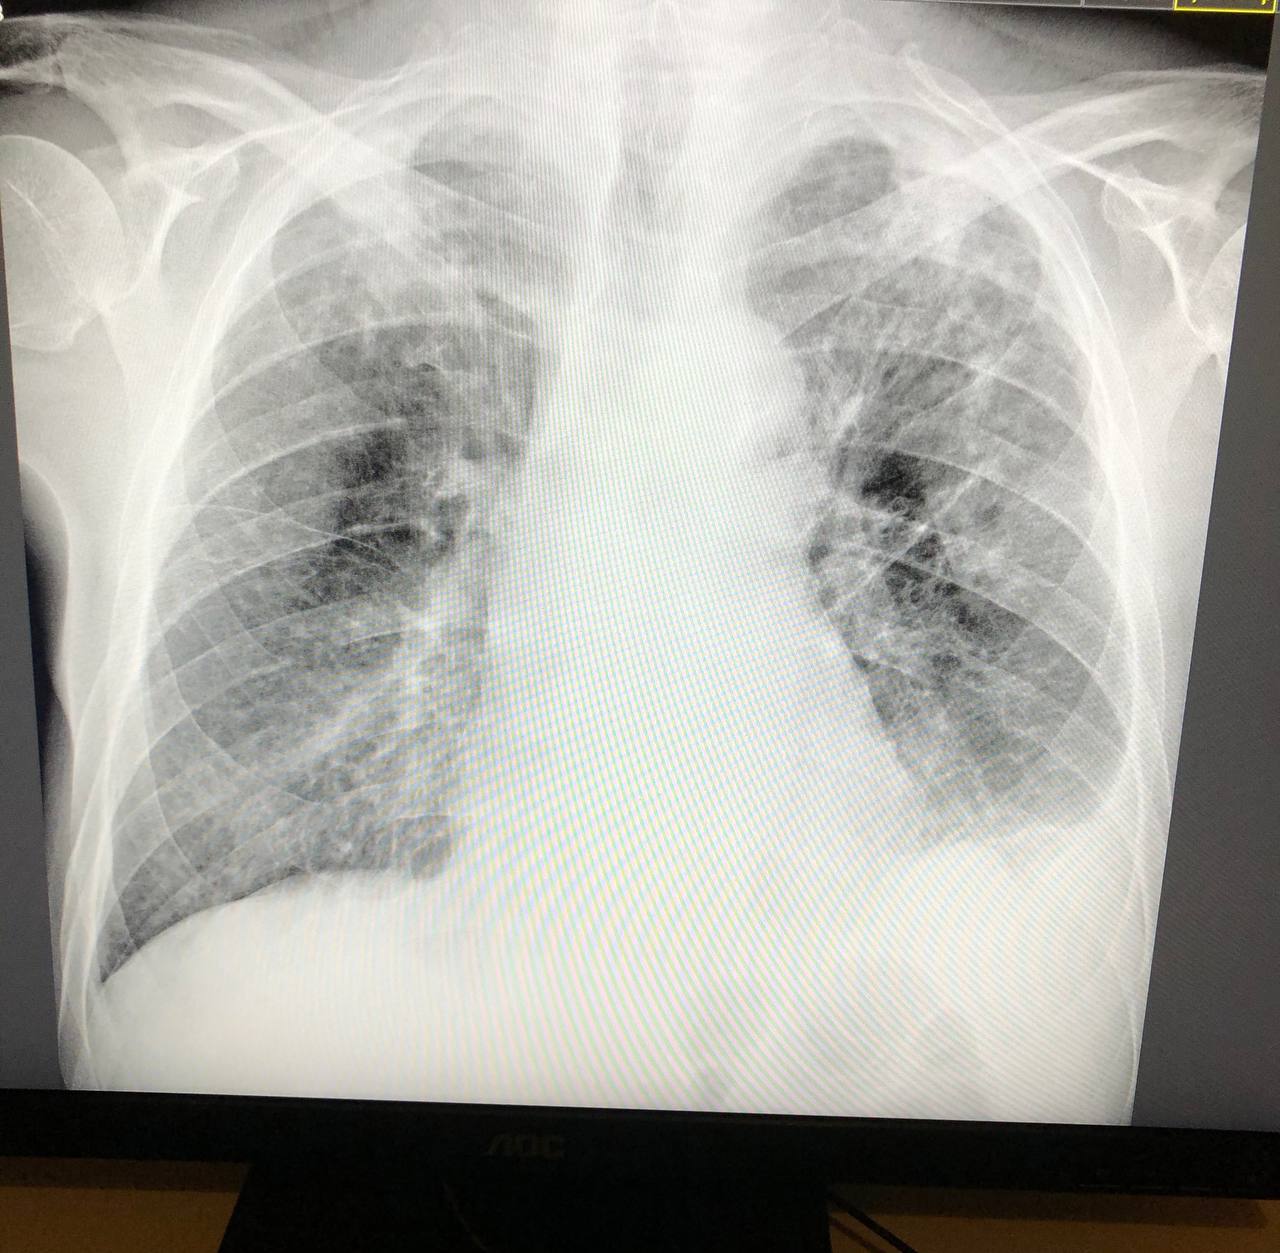

Доброй ночи коллеги, прошу прощения за беспокойство. Пациент 1943г, темп однократно 37. Похоже плеврит слева. Плюс тени с двух сторон плотные? К фтизиатру или больше за пневмонию? Подскажите пожалуйста. Спасибо вам большое.

последствия спецпроцесса, но связь с корнем есть

к фтизиатру